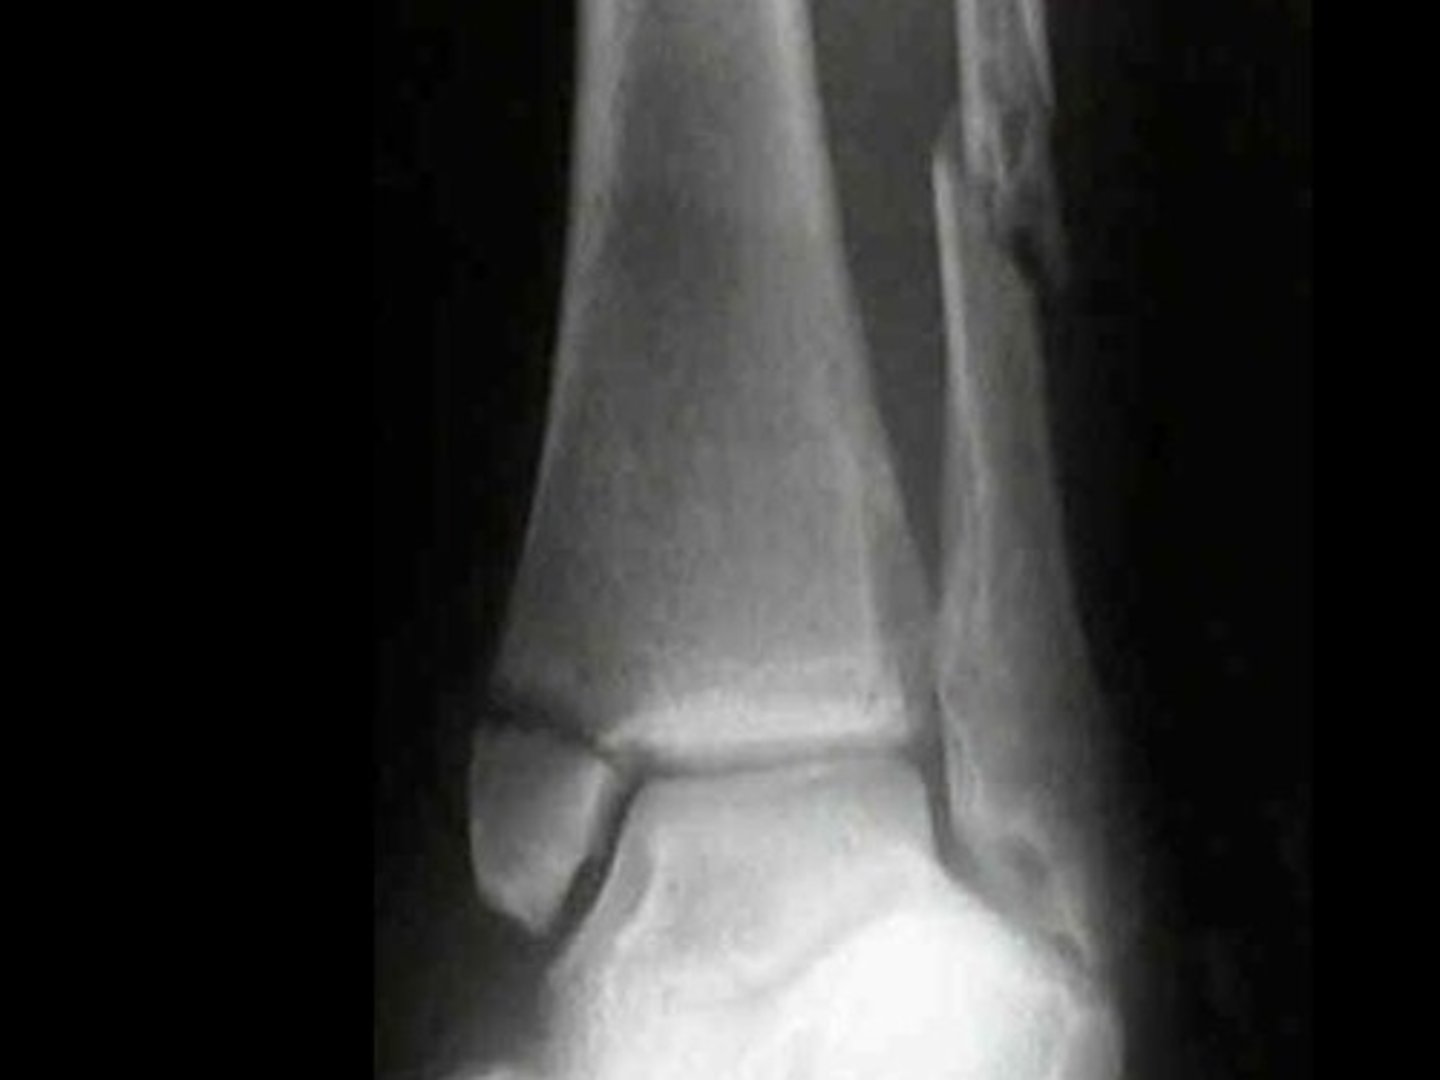

Complete fracture of distal fibula, frequently with fracture of medial malleolus

Pott's fx